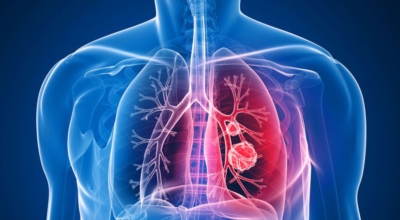

폐암은 폐에 생긴 악성 종양입니다. 폐 자체에 나타나는 원발성 폐암과 다른 장기에서 전이되어 온 전이성 폐암이 있습니다. 전 세계적으로 해마다 130만 명이나 되는 사람들이 폐암으로 사망하는데 이는 암에 의하여 사망하는 것 중에 가장 높은 비중을 차지하고 있습니다.

폐암 초기증상으로는 가슴통증이 있습니다. 폐암 환자들의 약 1/3 환자들이 흉통을 호소해요. 흉통이 발생하는 이유로는 폐의 가장자리 부분에 종양이 생기고 그 종양이 암세포를 생성하면서 흉벽과 흉막에 안착해서 통증을 일으키기 때문입니다.

흉통의 경우 여러가지 종류의 이유가 있을 수 있지만 우리가 오늘 다루는 폐암으로 기인해서 생기는 흉통은 계속적으로 쿡쿡 찌르는 느낌의 통증과 가벼운 통증이 아닌 둔탁한 통증을 동반하므로 유의하시길 바랄게요.